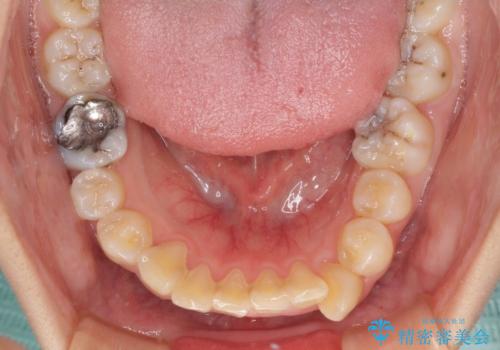

非常に大きな虫歯のあった下顎大臼歯は、根管治療を行い、矯正治療後にオールセラミッククラウンにて補綴治療を行いました。

当初予定では3年以上かかるとお伝えしておりましたが、スムーズに歯列が整い、2年強で終了することができました。